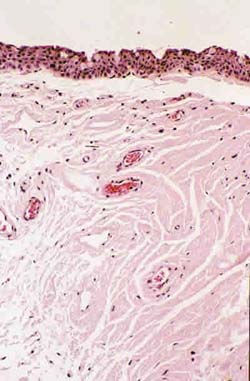

Las radiaciones ultravioleta no penetran con profundidad en los tejidos humanos, de modo que las lesiones que producen ocurren principalmente en la piel y en los ojos. La mayoría de…